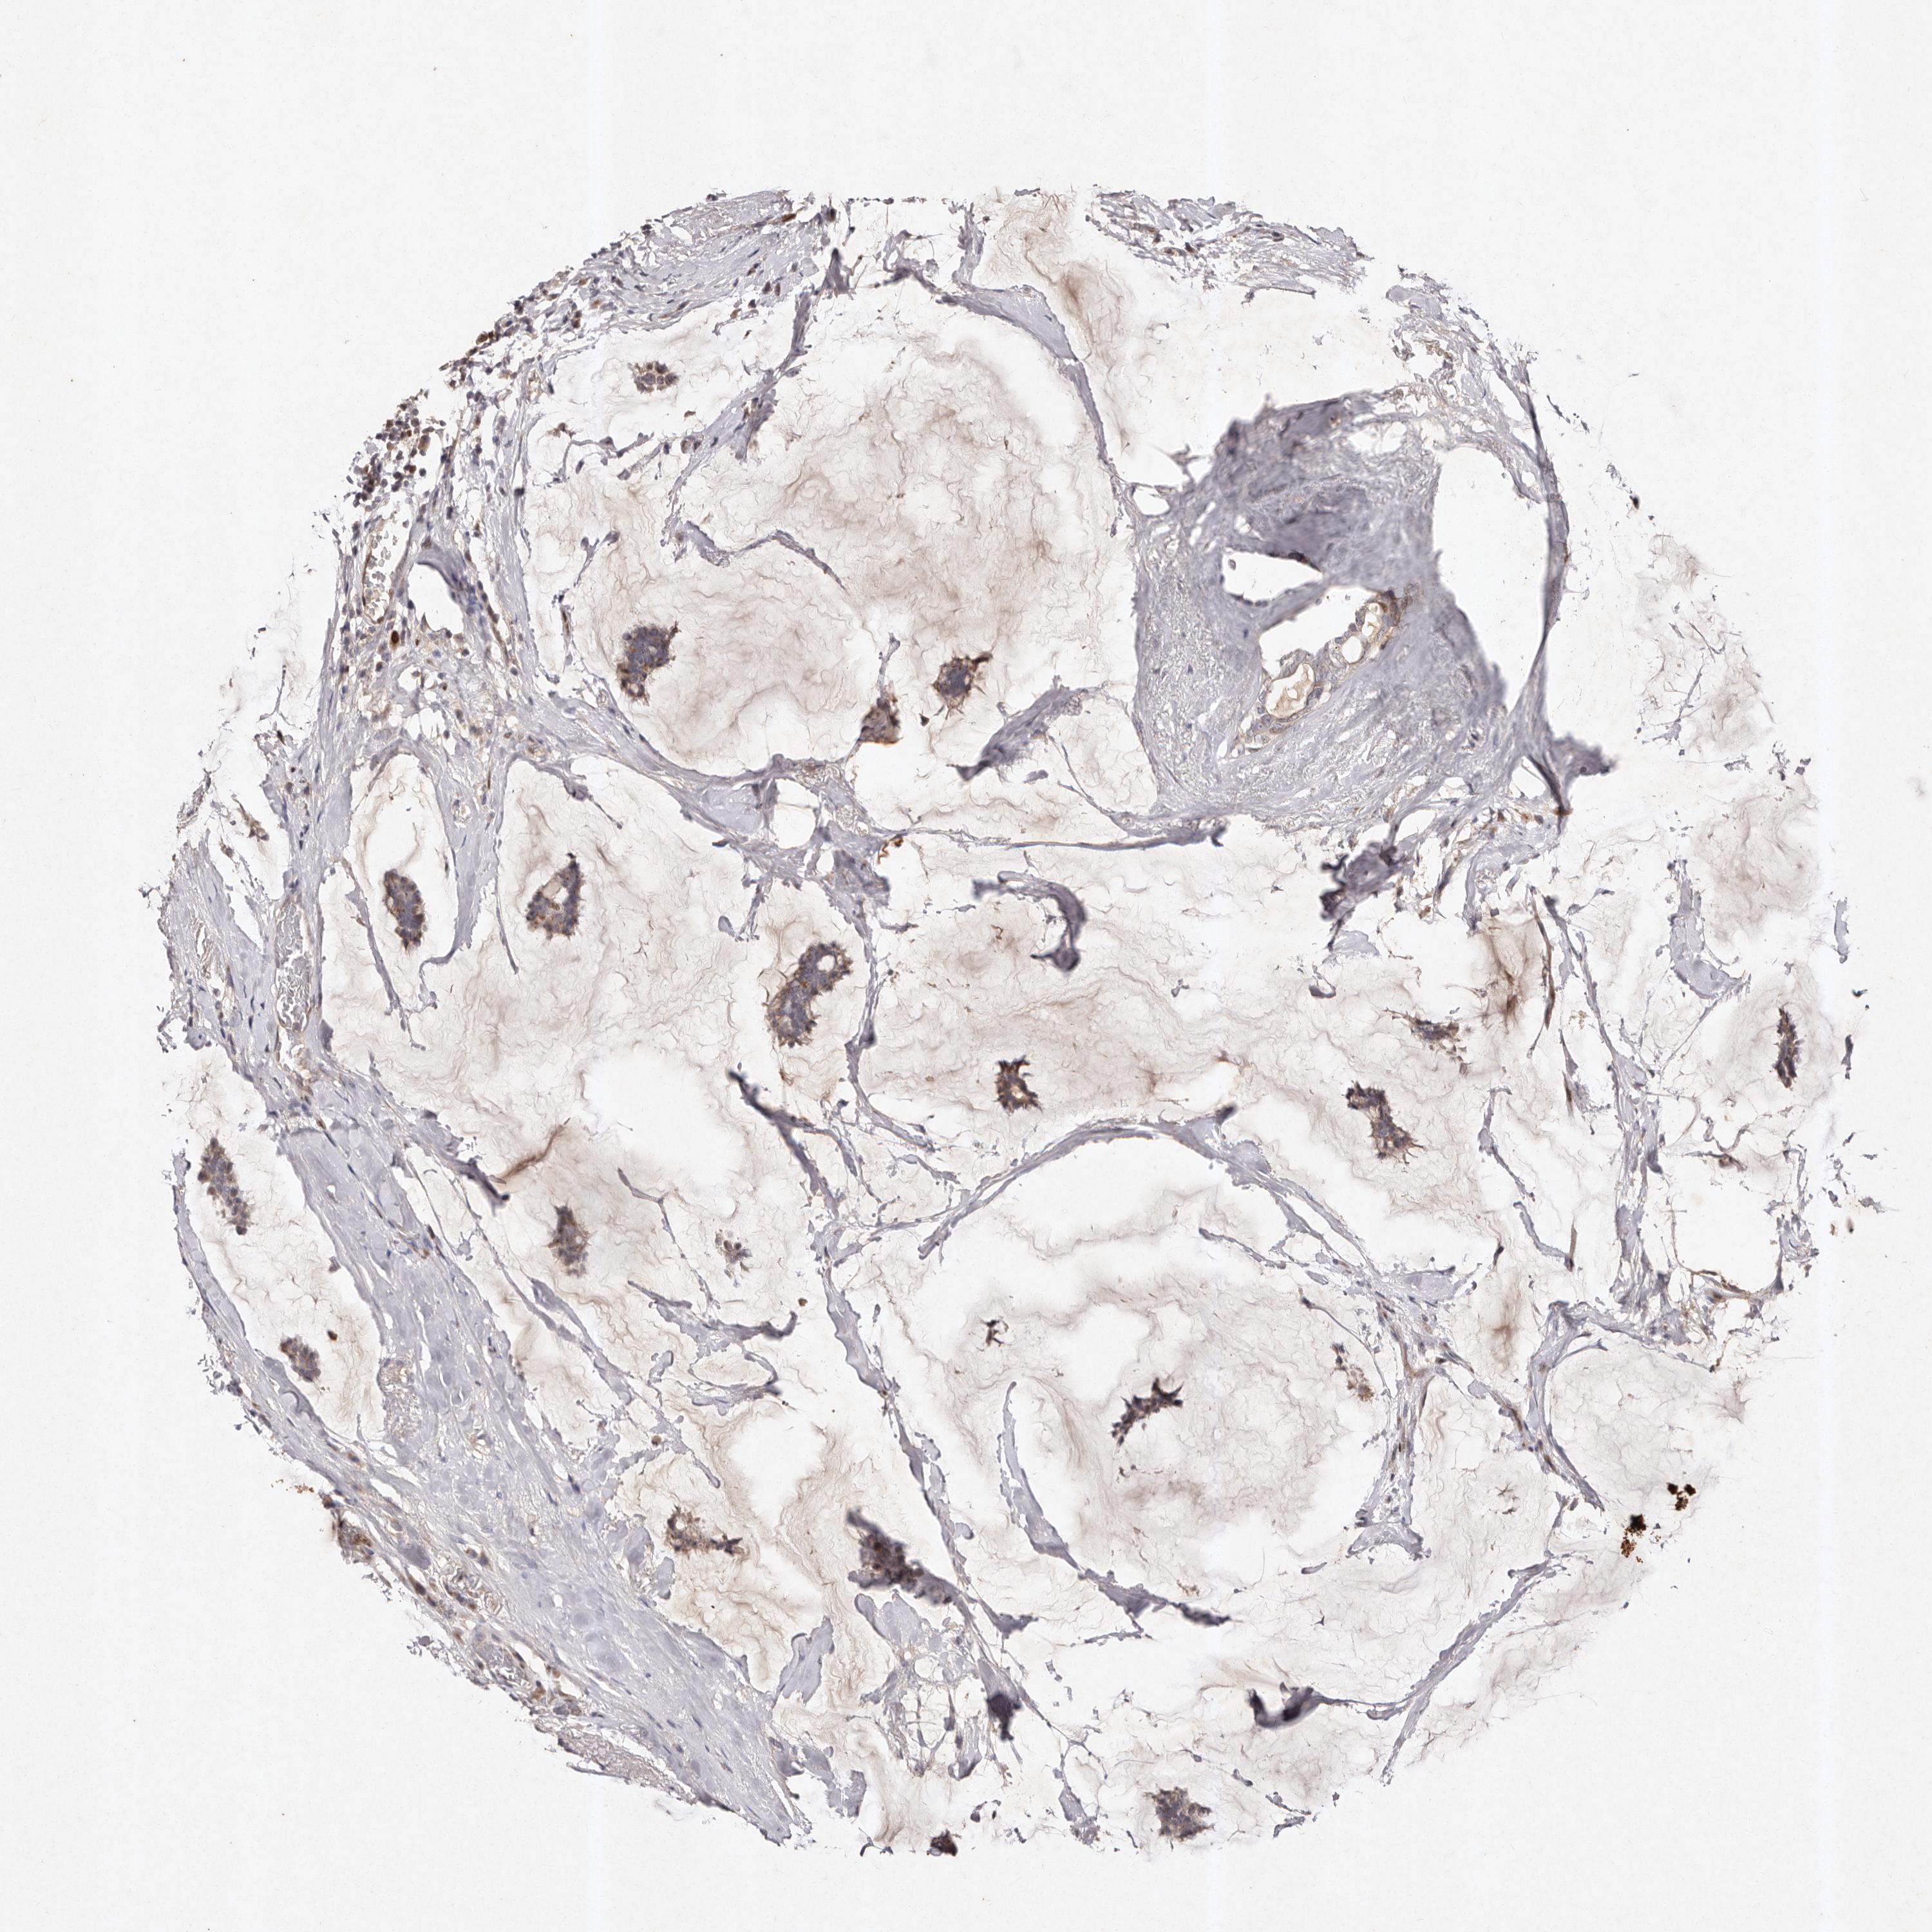

CANCER BREAST CANCER Show tissue menu

BRCA TCGA BRCA VALIDATION PROTEIN EXPRESSION